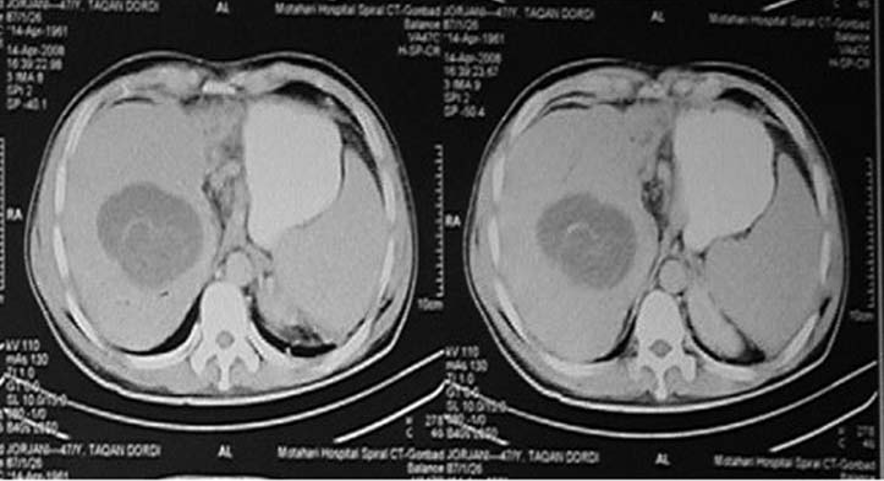

Pyogenic Liver Abscess

–Bacterial infection, often biliary source

–May be multiple lesions

–Thick wall with double target sign

–Gas may be present

–Common in diabetics

–Requires antibiotics ± drainage

Solitary cystic liver lesion with low attenuation center and peripheral thick enhancing wall.

CT Findings are consistent with amebic liver abscess.

Contrast-enhanced computed tomography of a 15-year-old female presenting with abdominal pain showing a well-circumscribed, unilocular, non-enhanced cystic lesion in the right lobe of the liver with typical “double-wall sign” of hydatid cyst (arrows).

Cyst in the liver with daughter cyst.